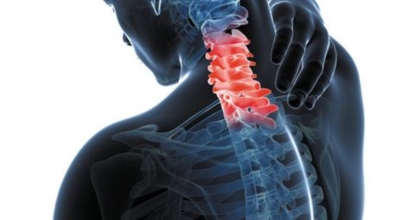

목 디스크 및 경추 추간판 탈출증 이라고도 하고 원진단명이 경추염좌로 나올 수 있어요. 최근에는 컴퓨터나 스마트폰을 많이 하므로 거북목 증상으로 고통을 호소하는 경우가 점점 늘어나고 있어요. 오늘은 목디스크 증상은 어떤 점이 있는지 알려드려요.

목디스크는 20대 이후에 자주 발생해요 그 이유는 목에 있는 디스크의 약화와 잘못된 자세에서 비롯되는 경우가 많습니다 위에서 언급드렸듯이 장기간 앉아서 근무한다면 좋지 않은 자세로 인해 목에 무리가 갈 수 있고 평상시에도 바른 자세를 유지하고 있는 것은 굉장히 고통스럽고 힘든 일이라서 목 통증이 느껴지는 건 당연하다고 볼 수 있어요.